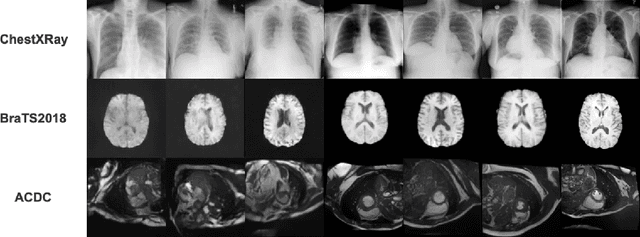

Abstract:In the realm of smart healthcare, researchers enhance the scale and diversity of medical datasets through medical image synthesis. However, existing methods are limited by CNN local perception and Transformer quadratic complexity, making it difficult to balance structural texture consistency. To this end, we propose the Vision Mamba DDPM (VM-DDPM) based on State Space Model (SSM), fully combining CNN local perception and SSM global modeling capabilities, while maintaining linear computational complexity. Specifically, we designed a multi-level feature extraction module called Multi-level State Space Block (MSSBlock), and a basic unit of encoder-decoder structure called State Space Layer (SSLayer) for medical pathological images. Besides, we designed a simple, Plug-and-Play, zero-parameter Sequence Regeneration strategy for the Cross-Scan Module (CSM), which enabled the S6 module to fully perceive the spatial features of the 2D image and stimulate the generalization potential of the model. To our best knowledge, this is the first medical image synthesis model based on the SSM-CNN hybrid architecture. Our experimental evaluation on three datasets of different scales, i.e., ACDC, BraTS2018, and ChestXRay, as well as qualitative evaluation by radiologists, demonstrate that VM-DDPM achieves state-of-the-art performance.